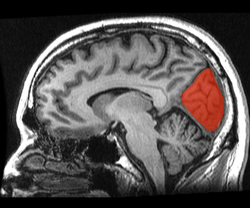

![]() Sagittal MRI slice with the cuneus and lingual gyrus shown in red. | |

The cuneus (Latin for "wedge"; plural, cunei) is a smaller lobe in the occipital lobe of the brain. The cuneus is bounded anteriorly by the parieto-occipital sulcus, inferiorly by the calcarine sulcus.

The cuneus (Brodmann area 17) receives visual information from the same-sided superior quandrantic retina (corresponding to contralateral inferior visual field). It is most known for its involvement in basic visual processing. Pyramidal cells in the visual cortex (or striate cortex) of the cuneus, project to extrastriate cortices (BA 18,19). The mid-level visual processing that occurs in the extrastriate projection fields of the cuneus are modulated by extraretinal effects, like attention, working memory, and reward expectation.